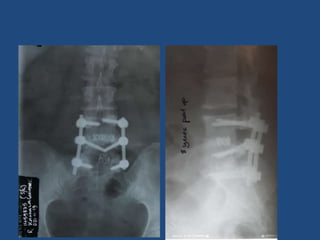

Infective spondilitis

TB Spine L3L4

Infective Discitis